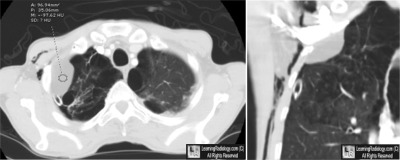

Additional Image-Axial Chest CT with Coronal Reconstruction

Axial Chest CT with Coronal Reconstruction

(Pay no attention to the subcutaneous emphysema and chest tube)

5. Pleural Lipoma

Pleural Lipoma

- Most common benign soft tissue tumors of the pleura

- Believed to originate in the parietal pleura extending into the subpleural, pleural, or extrapleural space

- Slow-growing, encapsulated

- May become quite large